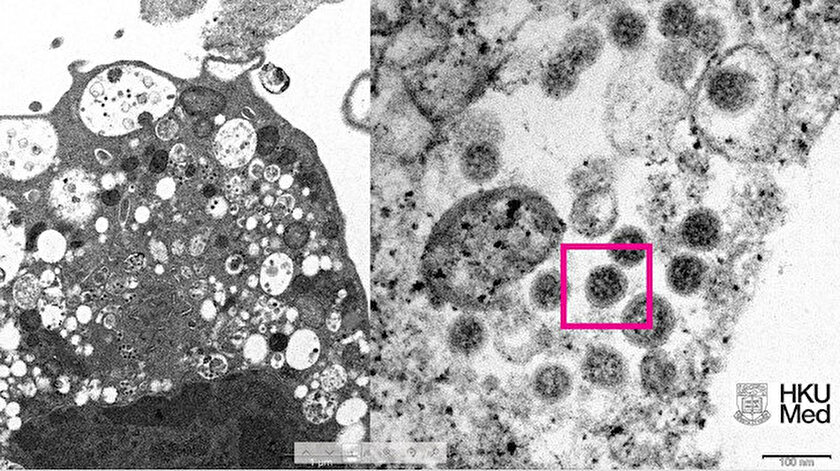

HKUMed’den yapılan açıklamada, araştırmacılar tarafından SARS-CoV-2 virüsünün Omicron varyantının elektron mikroskobu görüntüsünün ortaya çıkarıldığı belirtildi.

Üniversite tarafından yayınlanan fotoğrafın solunda, küçük siyah viral partiküller içeren şişmiş veziküllerle hücre hasarını gösteren, SARS-CoV-2 Omicron varyantı ile enfeksiyondan sonra bir maymun böbrek hücresinin (Vero E6) düşük büyütmeli elektron mikrografının yer aldığı ifade edildi.

Fotoğrafın sağında ise yüzeylerinde korona şekilli sivri uçlara sahip viral partikül kümelerini gösteren enfekte bir Vero E6 hücresinin yüksek büyütmeli elektron mikrografının yer aldığı belirtildi.